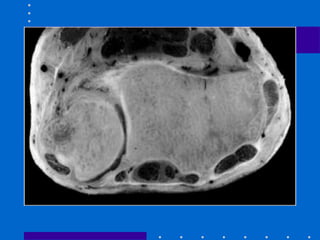

Anatomia Óssea

• Rádio distal

# metáfise: cortical mais fina dorsal e radial.

Colapso das fraturas dorsal e radial

#Faceta escafóide

#Faceta lunar

#Incisura sigmóide

• Estilóide radial roda palmarmente 15º fora

do eixo do rádio, isso dificulta acesso por

abordagem dorsal ao estilóide

• Cortical óssea mais forte palmar e ulnar

• Parâmetros: comprimento radial(12 mm),

angulação radial( 23º) e inclinação palmar

(11 a 12 º)

• NO AP: osso mais forte subjacente à faceta

lunar do rádio

• Inserção dos ligamentos R-U distais

palmares e para o lig radiolunar mais forte

• Deslocamento deste fragmento leva a

restrição da rotação e deslocamento palmar

do carpo